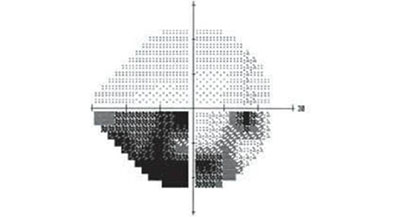

視野指的則是眼睛看向正前方時所能看到的空間范圍。在檢查中,視野常被劃分為四個象限,下圖就是一位青光眼患者的視野檢查結果,圖中黑色部分為視野缺損的部分。